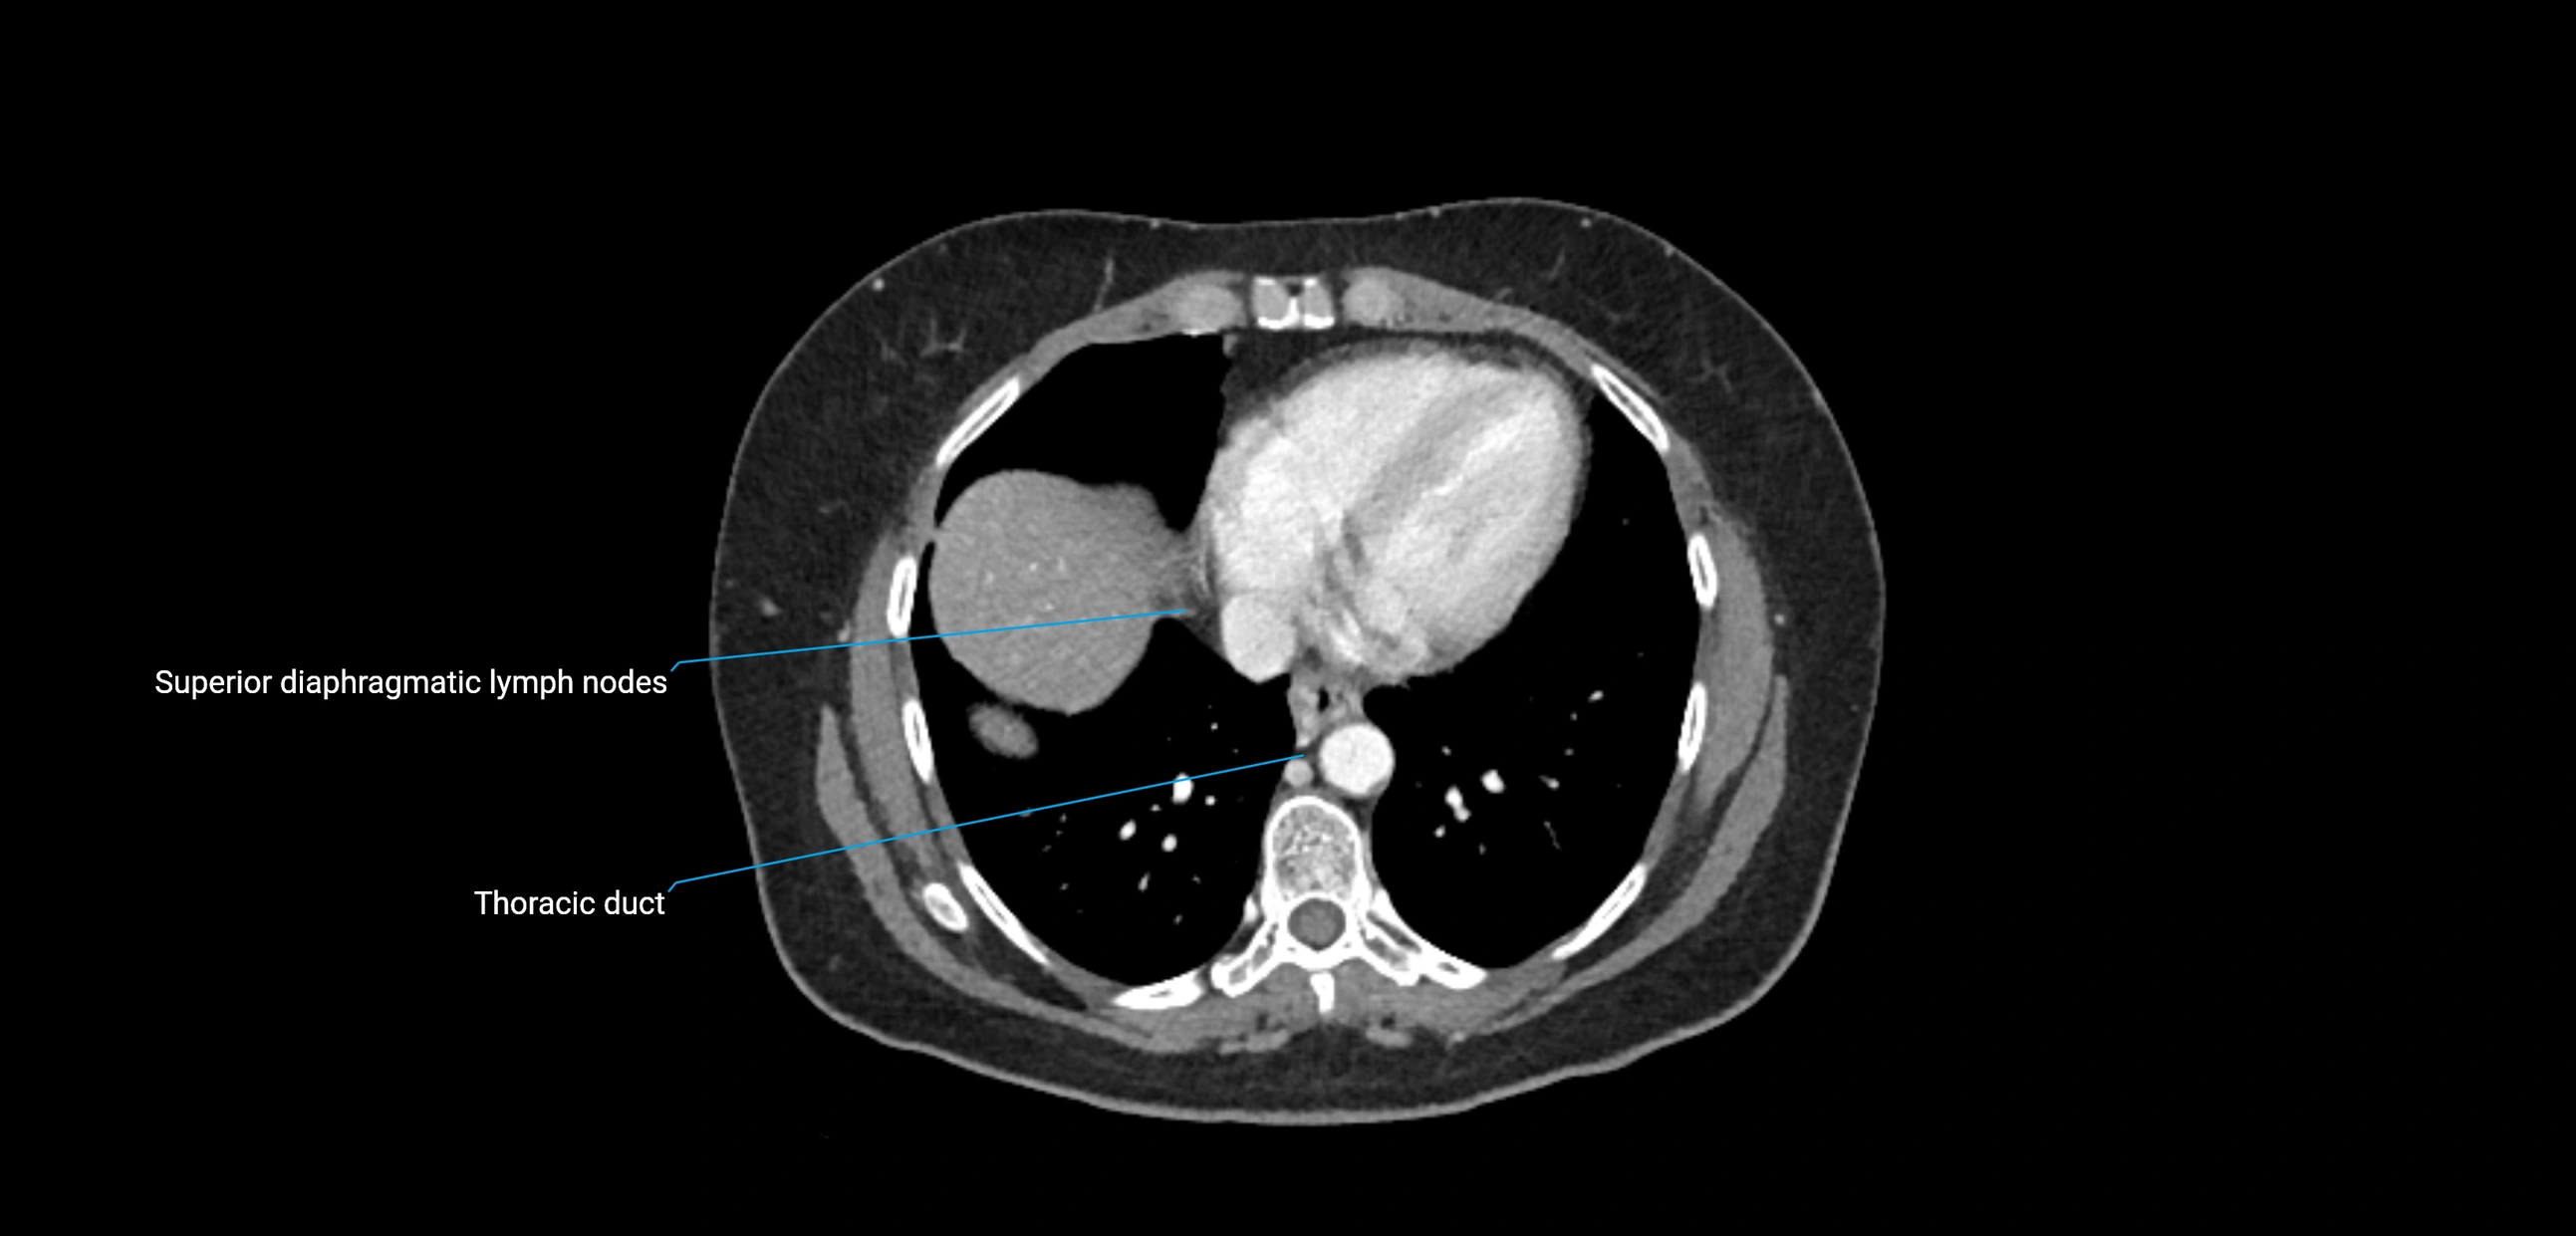

MRI images

image